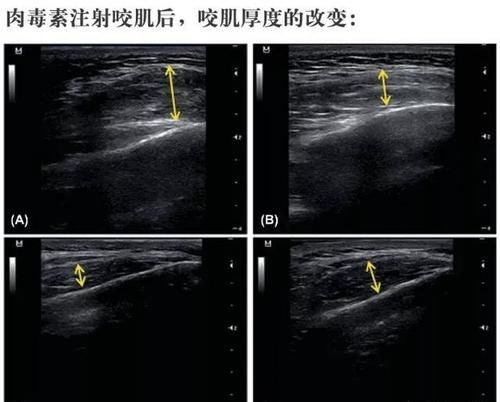

·咬肌发达:

咬肌肥厚导致,呈现方脸,咬牙时可以在耳下摸到明显凸起。

最好解决的是咬肌,注射个瘦脸针就可以很快见效,效果又很好,可以维持4-6个月左右;